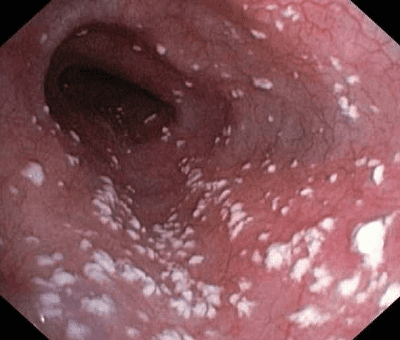

Молочниця в роті

Цей вид захворювання зустрічається у 50% заражених грибковою інфекцією. Ні в кого немає відмінностей у проявах цієї форми. Спочатку з’являється почервоніння на слизовій оболонці внутрішньої поверхні щік, ясен, спинки язика, слизові оболонки потовщуються, сверблять. Потім стан погіршується білим творожистим нальотом, кислим запахом з рота, болем, зміною смаку або повною відмовою від їжі. Грибковий наліт не можна видалити простим зішкрібком або протиранням. Поверхня тканин травмується і кровоточить. Несвоєчасне лікування може призвести до субфебрильної t (38-38,5 С), набряку підщелепних лімфовузлів.